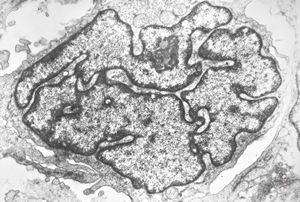

M, 70y. | mycosis fungoides - Sézary cell